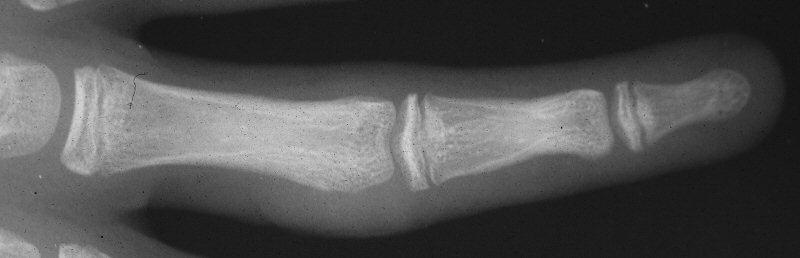

Case 2. Mass developing after a lateral dislocation of the proximal  interphalangeal joint of a 34 year old woman.

Radiographs were consistent with either a united collateral ligament avulsion fracture or ossiification of a parosteal hematoma.

This was treated with simple excision and collateral ligament repair to local tissues.

Late result.